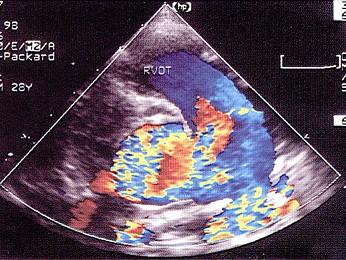

该病例最可能的诊断?(?)A.动脉导管未闭B.共同动脉干C.主肺动脉间隔缺损D.大动脉异位E.肺动脉狭窄

问题 该病例最可能的诊断?(?)

选项 A.动脉导管未闭 B.共同动脉干 C.主肺动脉间隔缺损 D.大动脉异位 E.肺动脉狭窄

答案 C